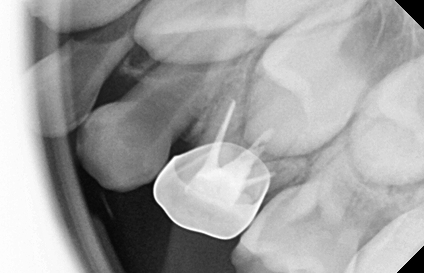

• 기성 금속관 수복

스테인리스로 만들어진 은색의 기성 크라운 보철로,

충치가 심하거나 신경치료한 유치 어금니를 전체적으로 씌워 보호하는 치료입니다.

유치 신경치료는 일반적으로 2회 내원 신경치료 및 크라운 치료까지 마무리 됩니다.

2차 내원에서는 국소마취 후 치아 모양을 정리하고,

미리 만들어진 크라운을 치아에 맞게 조정한 후 접착하여 마무리합니다.